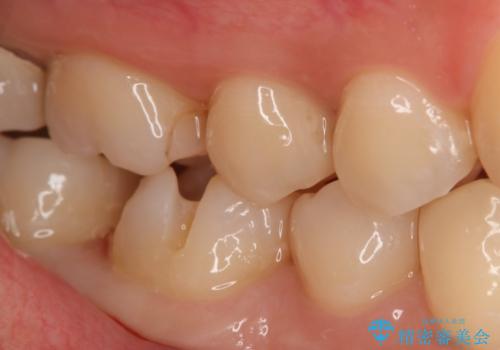

- 右下大臼歯の保険材料劣化に伴う虫歯の治療を希望された患者さまです。

審美性や精度の高い治療を希望されたので切削量や形態を考慮し、セラミックインレーでの治療を選択しました。

保険治療で使用される材料は劣化しやすく直下で虫歯が進行していることが多いです。

今回の患者さまは遠心部の虫歯が深かったのでCRで裏層した上で形成・印象を行いインレーセットを行っています。